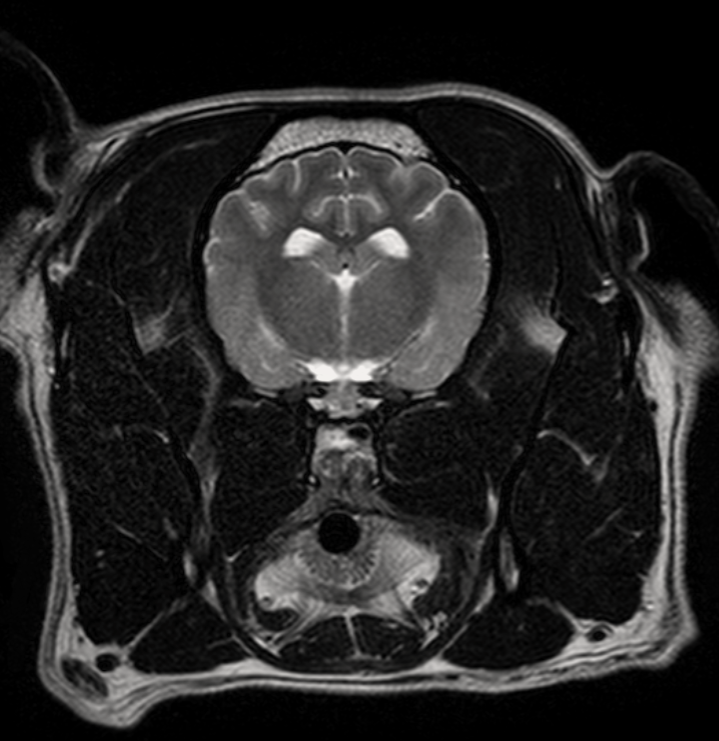

МРТ исследования проводятся на аппарате высокого качества Phillips Intera с напряженностью магнитного поля 1,5 Тесла. Позволяет максимально точно визуализировать анатомические структуры одинаково хорошо животному от 200г до 200кг

- Проведение мрт животному